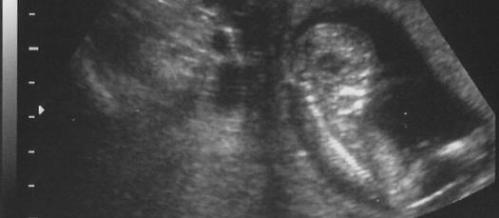

So, she went to her gynecologist (a gynecologist is a doctor only for women) and the gynecologist gave her an ultrasound.

An ultrasound is a machine that lets the gynecologist look inside Christine's stomach. It uses sound waves. At the top of this post on the blog there will be a picture of our most recent ultrasound. It's how you can see inside a woman to see how the baby is progressing. And the ultrasound showed that Christine was pregnant. And, of course, then we were excited.